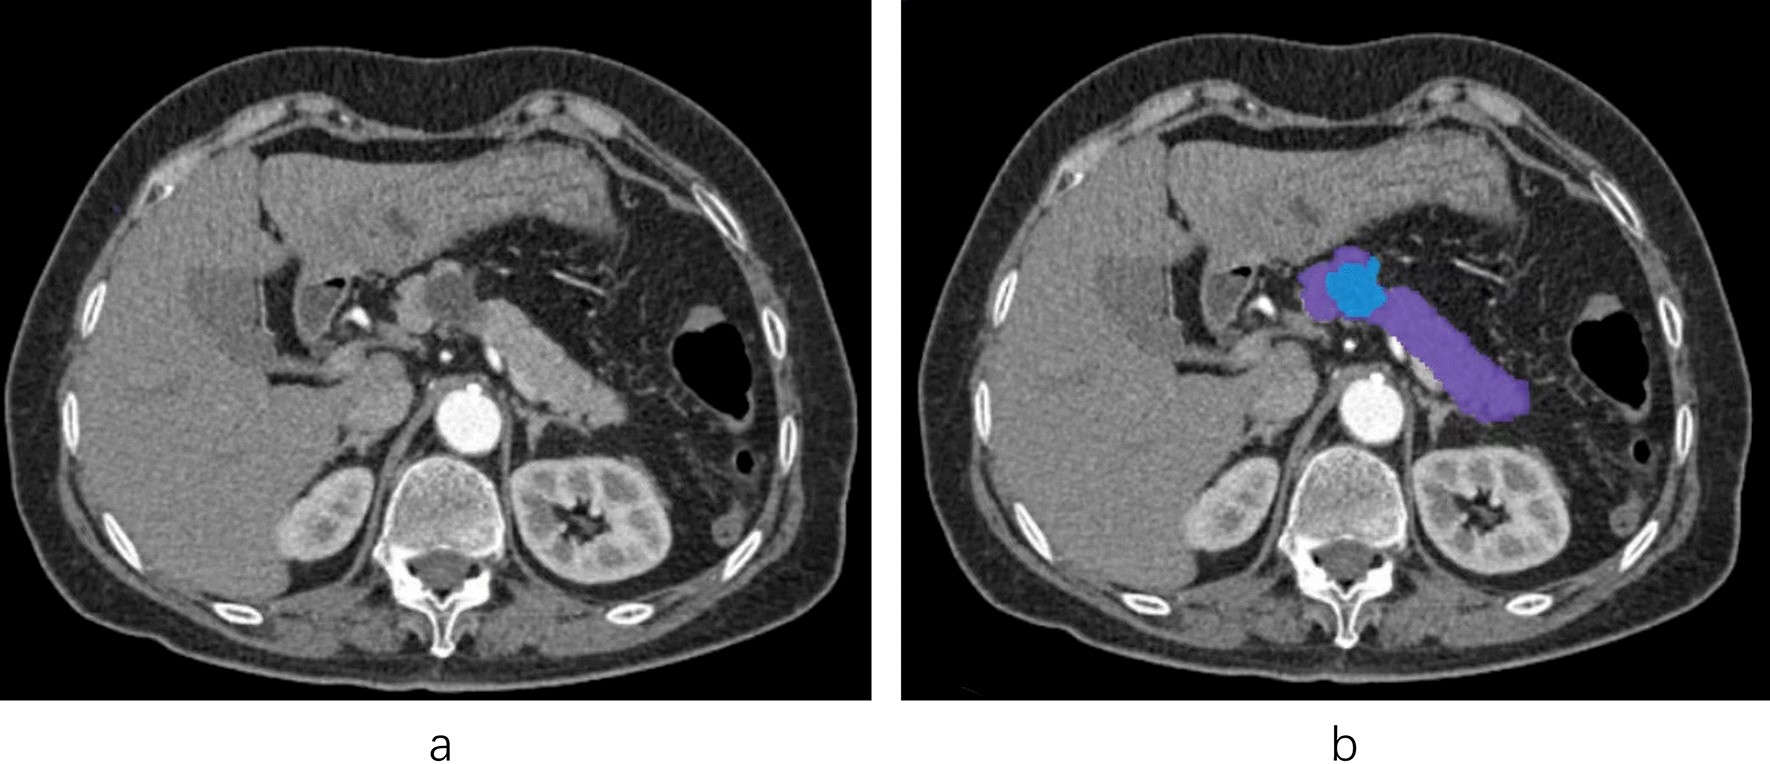

Figure 1

The segmentation of pancreatic lesion. (a) The arterial-phase enhance CT of pancreas (b) Blue part is the lesion region. Purple part is the remaining pancreatic region. The RIAS software extracts radiomic features by labeling the purple and blue areas.